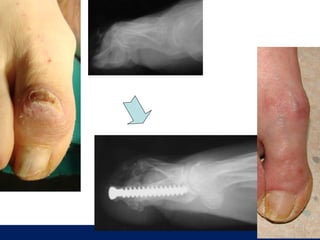

OLGU No 5   H.G., 26y, K

ÖĞÜT

Postop 3. ay

Postop 6. ay